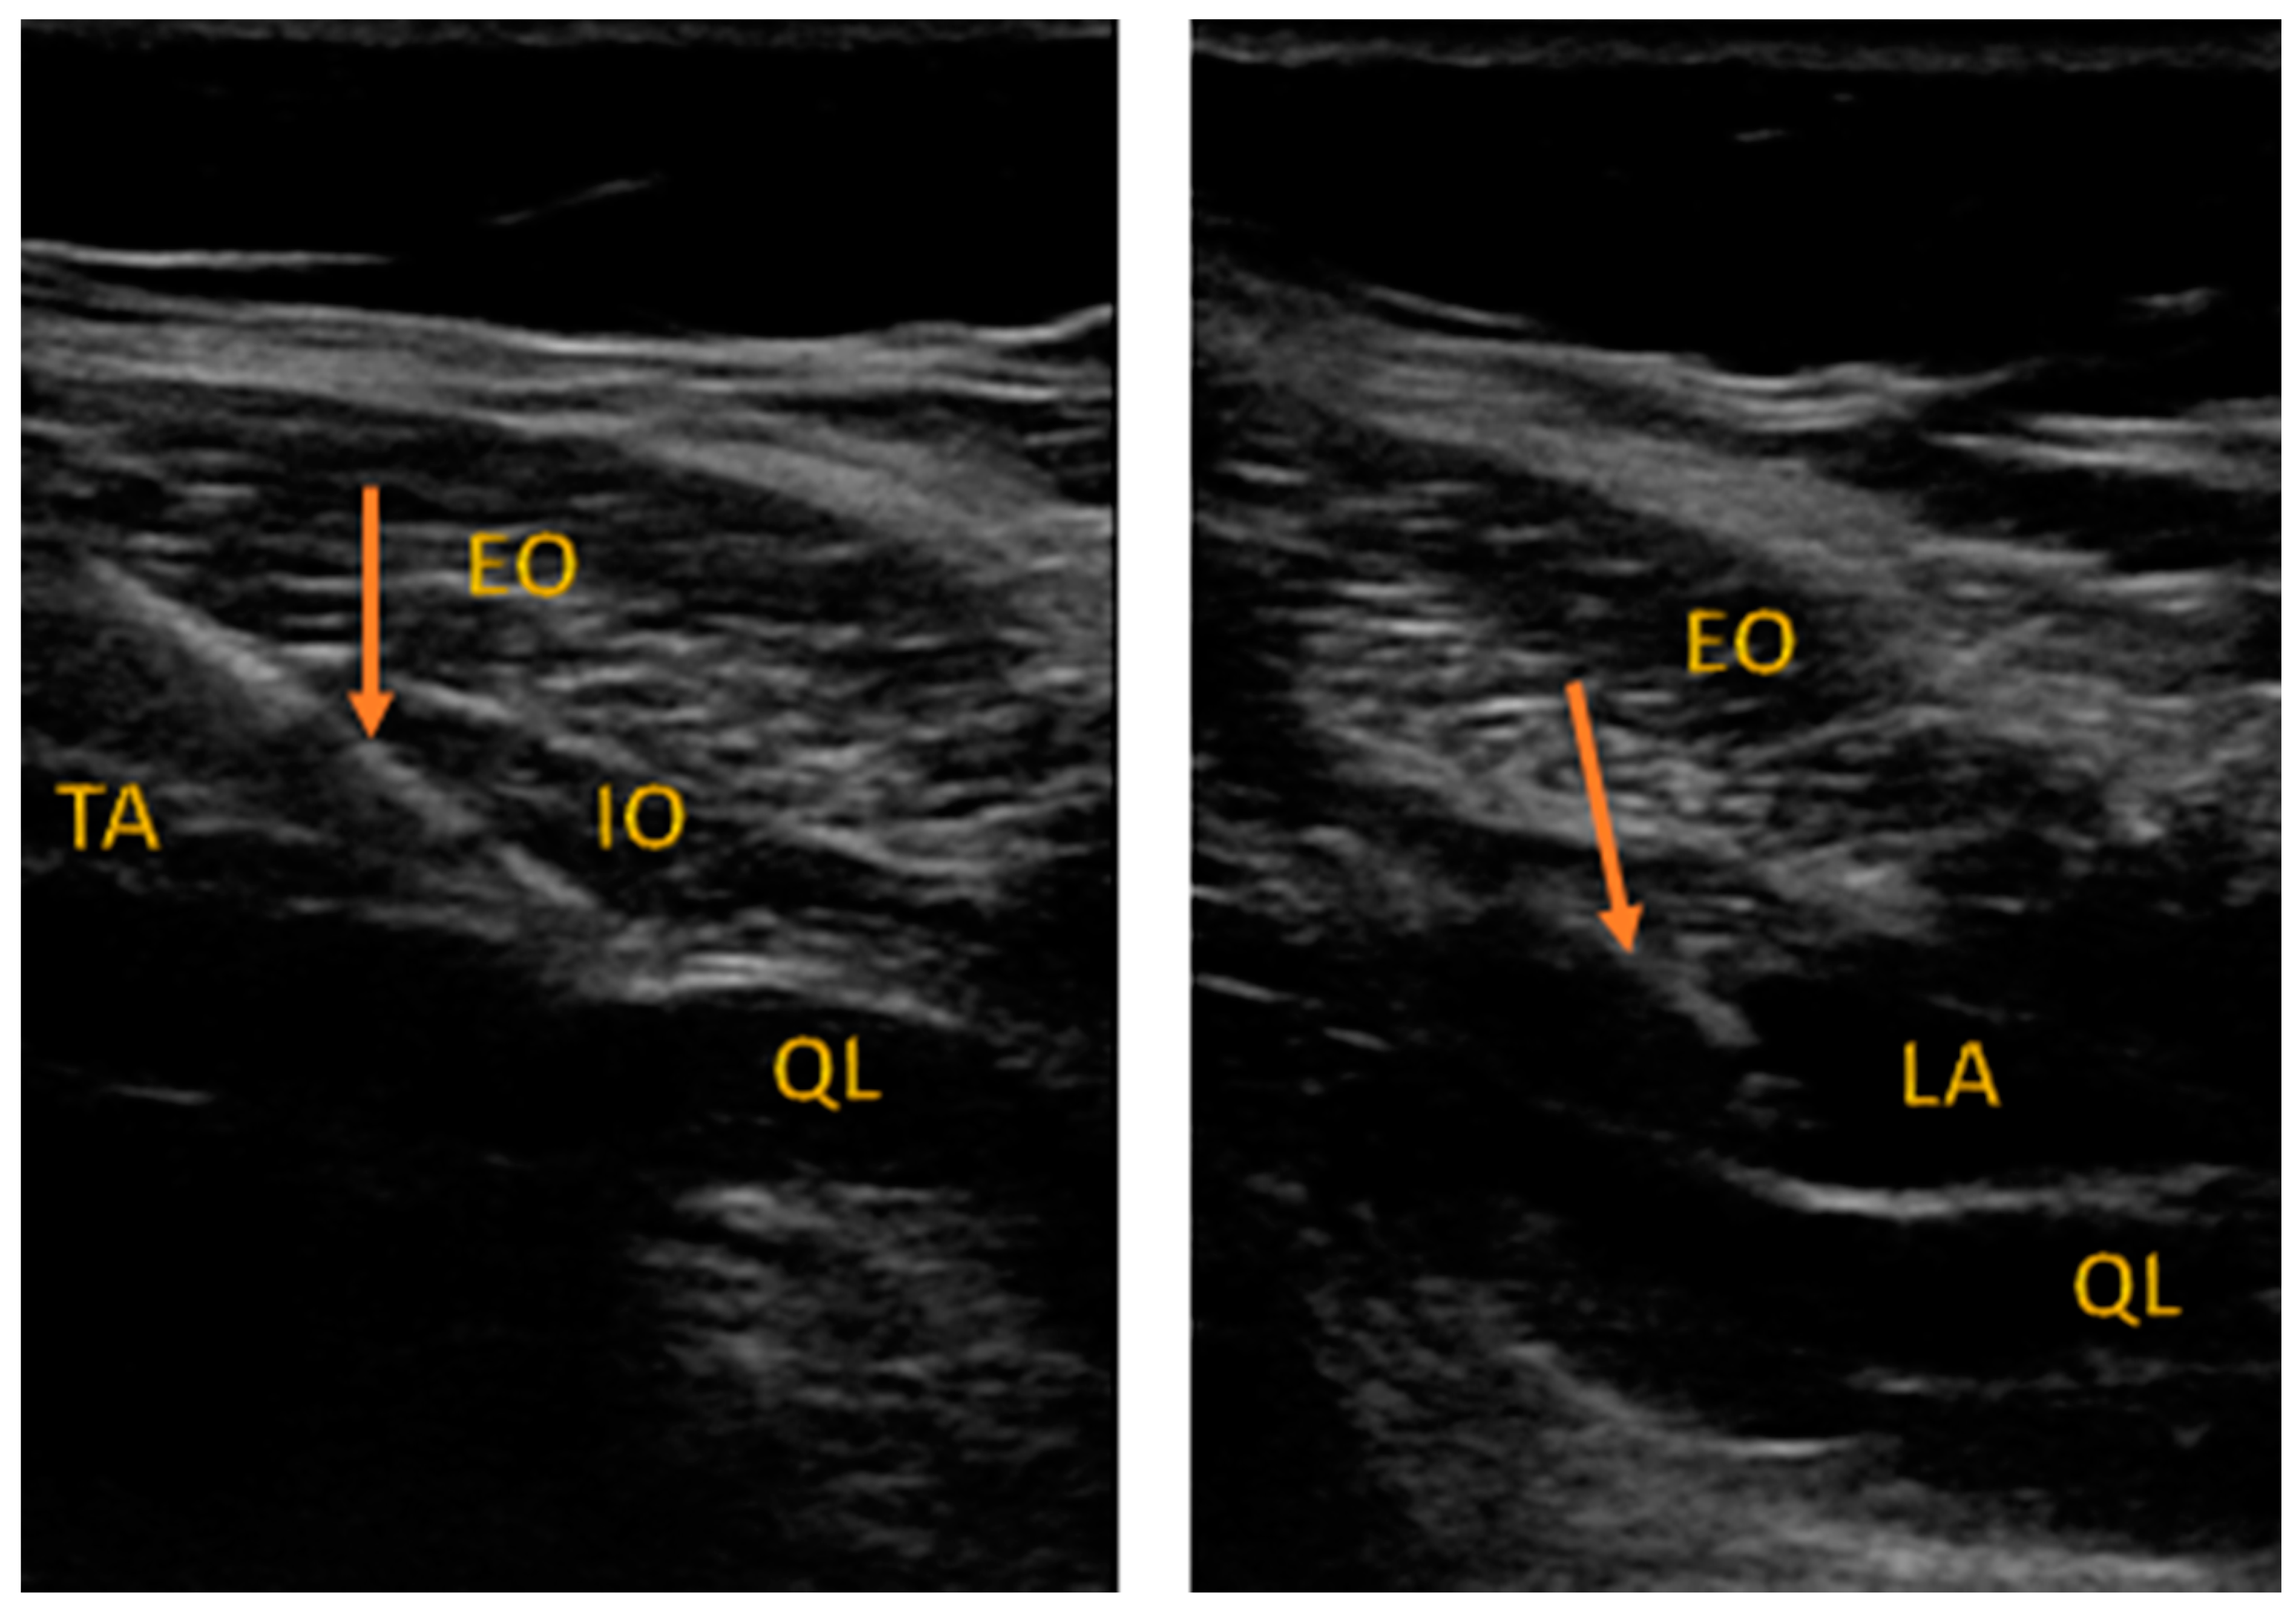

2.2. Anesthesia and Regional Block